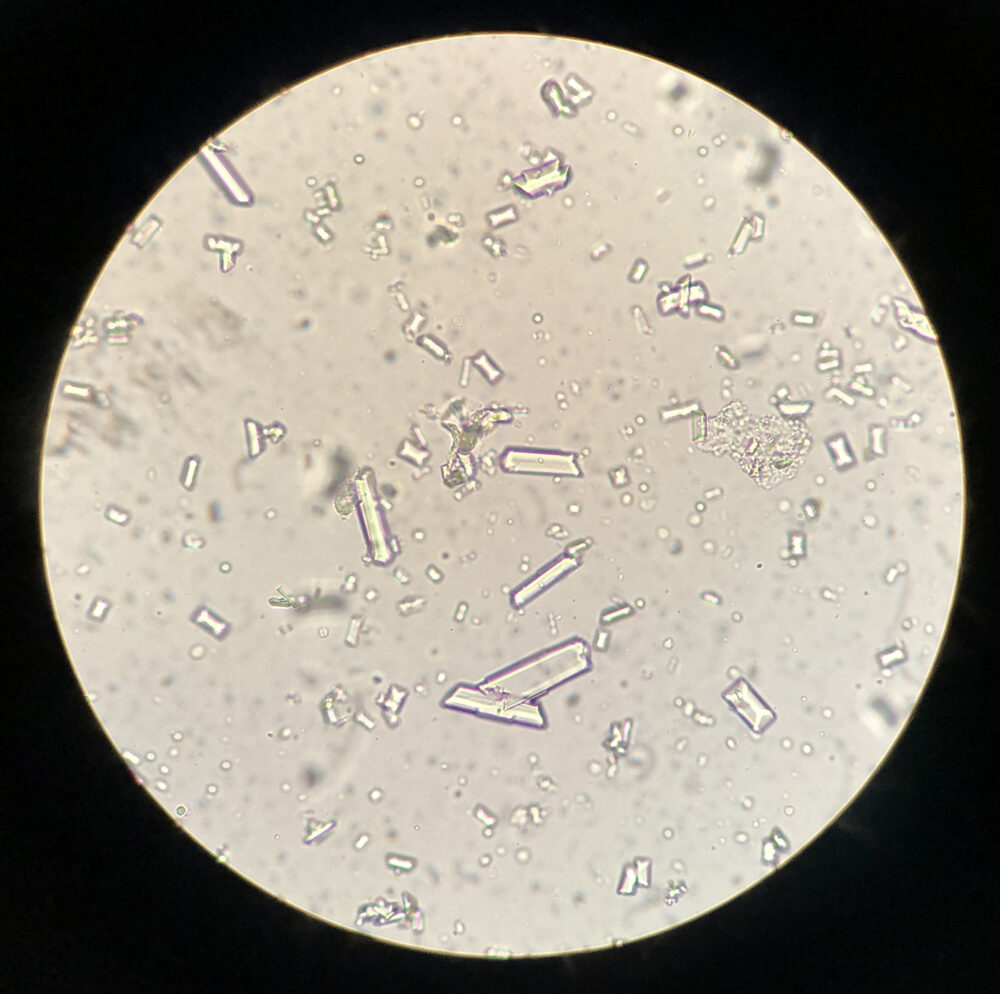

In de blaas en nieren van honden en katten (maar ook van konijnen en cavia’s ) kunnen er kristallen gevormd worden, wat er uit kan zien als fijn zand of gruis. Dit kan worden gevormd door verschillende soorten kristallen. Blaasgruis kan een probleem vormen als het een verstopping van de plasbuis veroorzaakt, maar kan ook aanleiding geven tot een blaasontsteking en irritatie van de plasbuis. Als blaasgruis langere tijd aanwezig is, kunnen de kristallen gaan samenklonteren en stenen vormen. Het meest voorkomende type kristal bij de kat is struviet, maar calciumoxalaat is een goede tweede.

Er bestaan nog veel andere vormen van blaasgruis kristallen, zoals o.a. cystine en uraten. Deze komen minder vaak voor, maar geven vergelijkbare problemen als bij calciumoxalaat.

Blaasgruis bestaat uit kristallen, die allemaal scherpe randjes en puntjes hebben. Als dit tegen de blaaswand of in de plasbuis komt, geeft dit allemaal kleine ontstekinkjes. Deze ontstekingen geven pijnlijkheid, aandrang tot plassen en bloed in de urine. Daarbij krijgen bacteriën de kans om in die kleine beschadigingen te gaan groeien en een bacteriële infectie van de blaas te veroorzaken.

De diagnose

De diagnose van blaasgruis en blaasstenen wordt meestal gesteld via verder onderzoek. Er wordt gestart met een urineonderzoek en met een therapie. Soms is dit onvoldoende om het probleem op te lossen en is er een echo nodig. Met deze echo kan er beter gekeken worden naar de inhoud van de blaas, hoe de blaaswand er uitziet en er kan een punctie gedaan worden van de urine, voor een eventueel bacterieel onderzoek.